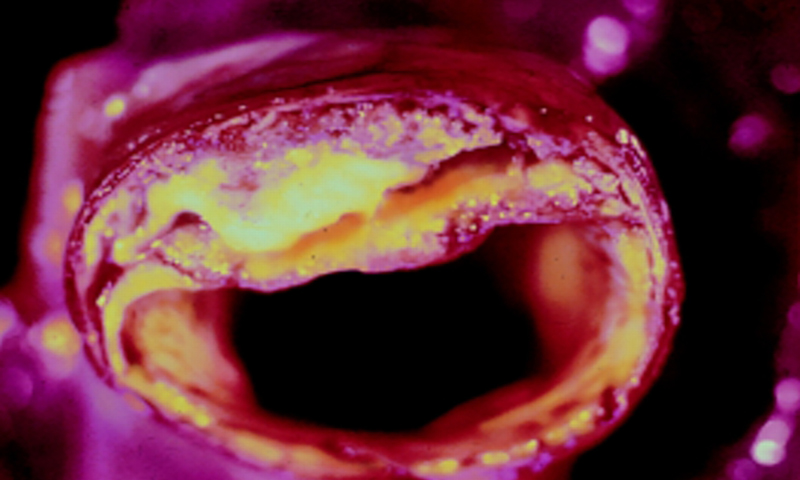

Si vos artères sont bouchées, sachez qu’il existe trois ingrédients efficaces qui peuvent améliorer, voire déboucher, les artères bouchées et éliminer la graisse du sang.

Les artères transportent les nutriments et l’oxygène vers le cœur et les autres organes du corps. Pour préserver votre santé, les artères doivent rester propres en permanence. C’est pour cette raison que l’alimentation est extrêmement importante pour vous et vos artères. Les produits transformés, les aliments gras, les toxines et les produits chimiques peuvent avoir des effets graves sur la santé cardiovasculaire et avec le temps ils peuvent entraîner des problèmes cardiaques graves.